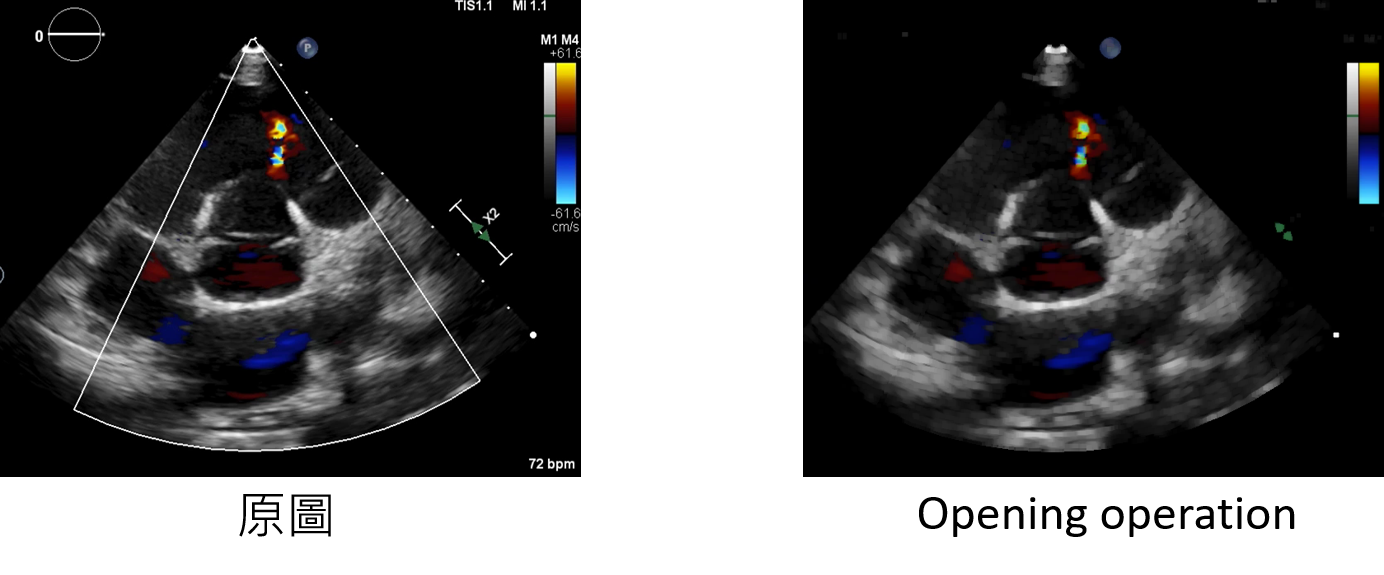

Opening_operation:增強方法

kernel:設定內核的大小

輸入範例:

datagen=CustomDataGenerator(fun="Opening_operation",kernel=5,dtype=int)